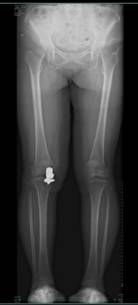

膝关节镜下前交叉韧带重建术 肩袖损伤修复术后

膝关节单髁置换术